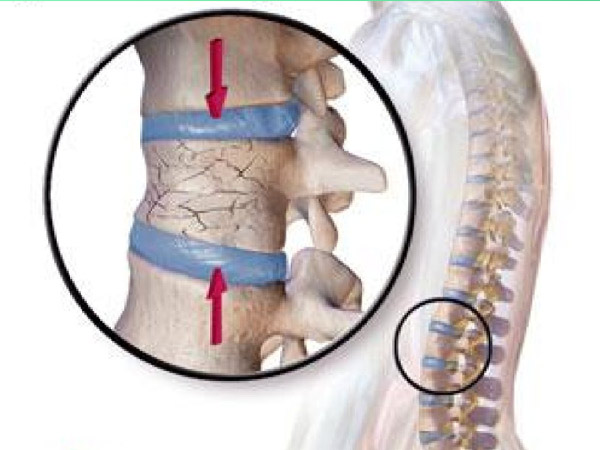

Tạo hình thân đốt sống bằng bơm cement sinh học qua cuống là một kỹ thuật ít xâm lấn, được thực hiện đầu tiên bởi Deramond và Galibert vào năm 1987 để điều trị u máu thân đốt sống. Sau đó kỹ thuật này được phổ biến rộng rãi khắp thế giới và được áp dụng trong điều trị các bệnh lý khác của cột sống như tổn thương di căn thân đốt sống hay xẹp đốt sống cấp tính do loãng xương. Cùng với sự già hóa dân số trên thế giới, xẹp đốt sống do loãng xương đang xảy ra ngày càng phổi biến [1]. Bơm cement sinh học và thân đốt sống giúp giảm đau hiệu quả ở những bệnh nhân xẹp đốt sống do loãng xương dựa vào cơ chế hóa học tại chỗ và nhiệt của polymethylmethacrylate (PMMA) lên đầu mút dây thần kinh của các mô xung quanh. Thêm vào đó cement trực tiếp làm vững đốt sống nhờ hàn gắn các đường vỡ và lấp đầy các vùng khuyết xương, điều này không thể có được khi điều trị bằng các thuốc thông thường [2], [3]. Những bệnh nhân loãng xương có thể bị xẹp ở một hoặc nhiều thân đốt sống, việc bơm cement ở 1 hoặc 2 tầng thân đốt sống đã được thực hiện rỗng rãi trên thế giới và đã chứng minh được tính ưu việt của nó qua rất nhiều nghiên cứu [4]. Việc bơm cement ở tối đa bao nhiêu tầng thân đốt sống trong một lần mổ vẫn còn bàn cãi, một số tác giả đề suất không nên bơm cement ở nhiều hơn 6 tầng thân đốt sống do có thể dẫn đến một số khó chịu trong mổ cho bệnh nhân khi phải nằm sấp lâu, tăng nguy cơ sảy ra một số biến chứng như tai biến của thuốc gây tê gây mê, cement trào ra ngoài, tắc mạch phổi …[5]. Chúng tôi đưa ra nghiên cứu này nhằm đánh giá tính an toàn và hiệu quả của bơm cement sinh học đa tầng thân đốt sống trên bệnh nhân xẹp đốt sống do loãng xương.